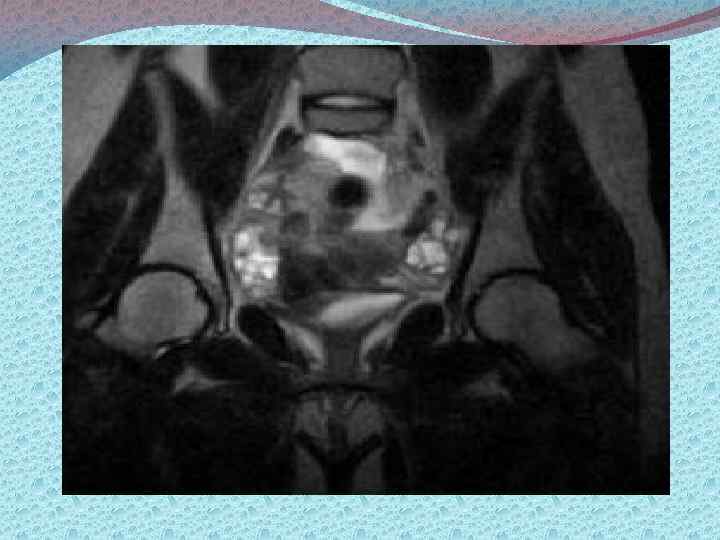

Методы диагностики: Визуализирующие: а)лучевые б)эндоскопические Лучевые: УЗИ, КТ, МРТ. Эндоскопические: лапароскопия, пункция заднего свода, забор материала для гистологического исследования. Лабораторные. Определение типов опухолевых маркеров: 1) онкофетальные и онкоплацентарные а/г (РЭА, АФП ХГЧ, ТБГ) 2) Опухолеассоциированные антигены (СА 125, СА 19 9, СА 72 4) 3) Ферменты (ПЩФ, НСЕ) 4) Гормоны (кальцитонин, эстрадиол, пролактин, ТТГ) 5) Продукты онкогенов 6) Белки острой фазы (ферритин, С реактивный белок, РЭА) 7) Биологически активные пептиды (ПГ, ГАГ, M CSF)

Стадирование злокачественных опухолей яичников: Первый этап: Физикальные методы обследования, в том числе осмотр шейки матки зеркалами; Са 125 в крови и моче; УЗИ органов брюшной полости, таза; Цитологическое исследование пунктата заднего свода влагалища Второй этап (для более точной оценки распространенности процесса, наличия метастазов): Компьютерная и магниторезонансная томография Рентгенография органов грудной клетки Цистоскопия, Внутривенная урография Сцинтография костей скелета